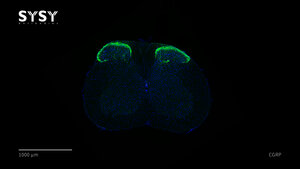

CGRP

414 004

Q99JA0

Mouse

spinal chord

Adult

Fluorescent

immunostaining